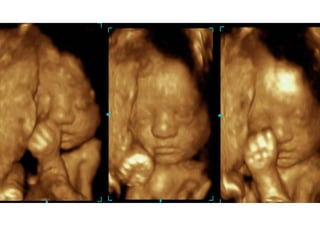

O QUE É?

 A ultrassonografia é o exame de ultrassom que utiliza ondas

sonoras para gerar imagens do corpo humano.

 É um método muito utilizado para o acompanhamento pré-natal e

para avaliação de estruturas de partes moles do corpo

humano.

 Além disso, também pode ser utilizado para guiar procedimentos

intervencionistas, como biópsias e cirurgias.

 É um procedimento seguro, de baixo custo, não invasivo e que

não utiliza radiação ionizante.

 Portanto, é uma ótima ferramenta diagnóstica.

Eles são utilizados para visualizar os

órgãos internos do corpo, como:

Coração e vasos sanguíneos, incluindo a aorta abdominal e seus principais ramos;

Fígado;

Vesícula biliar;

Baço;

Pâncreas;

Rins;

Bexiga;

Útero, ovários e, em pacientes grávidas, o feto;

Olhos;

Glândulas tireóide e paratireóide;

Bolsa escrotal (testículos).